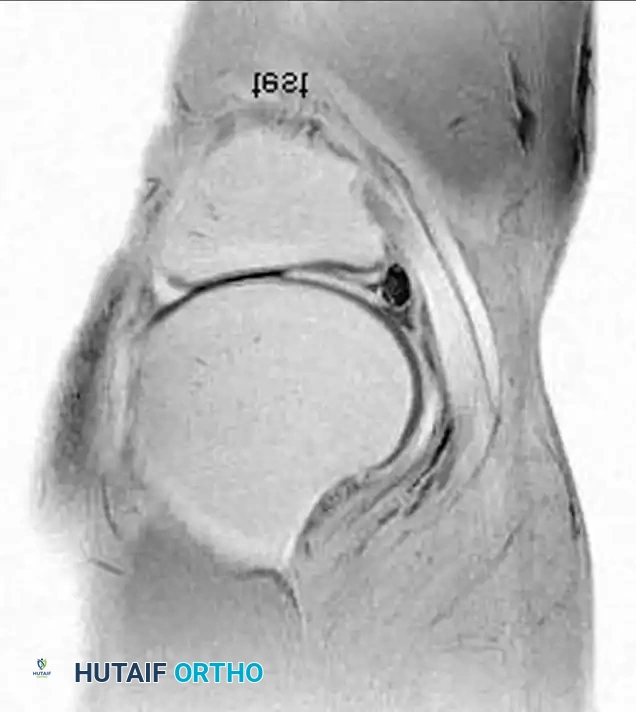

هناك أيضا تشوهات خلقية مثل الغضروف الهلالي القرصي، حيث يكون الغضروف سميكا ومسطحا بدلا من شكله الهلالي الطبيعي، وهو أكثر شيوعا في الجهة الخارجية للركبة.

ما هو الغضروف الهلالي القرصي؟

هو عيب خلقي يولد به الشخص، حيث يكون الغضروف الخارجي للركبة سميكا وعلى شكل قرص بدلا من شكل الهلال الطبيعي. قد لا يسبب أي مشكلة، ولكنه أكثر عرضة للتمزق مقارنة بالغضروف الطبيعي.